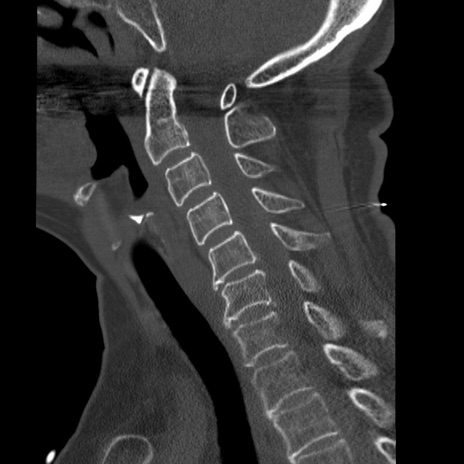

症例50 頚椎CT(矢状断像)

【症例】60歳代女性

【主訴】後頭部〜右後頸部にかけての痛み

【現病歴】本日飲食店でコーヒーを飲んでいたところ、突然後頭部〜右後頸部にかけて痛みが出現し、右上肢の感覚障害を伴ったため救急要請。

【身体所見】脳神経学的に明らかな異常所見を認めず。右上肢に軽度の感覚障害あり。

異常所見と診断は?

頚椎CT